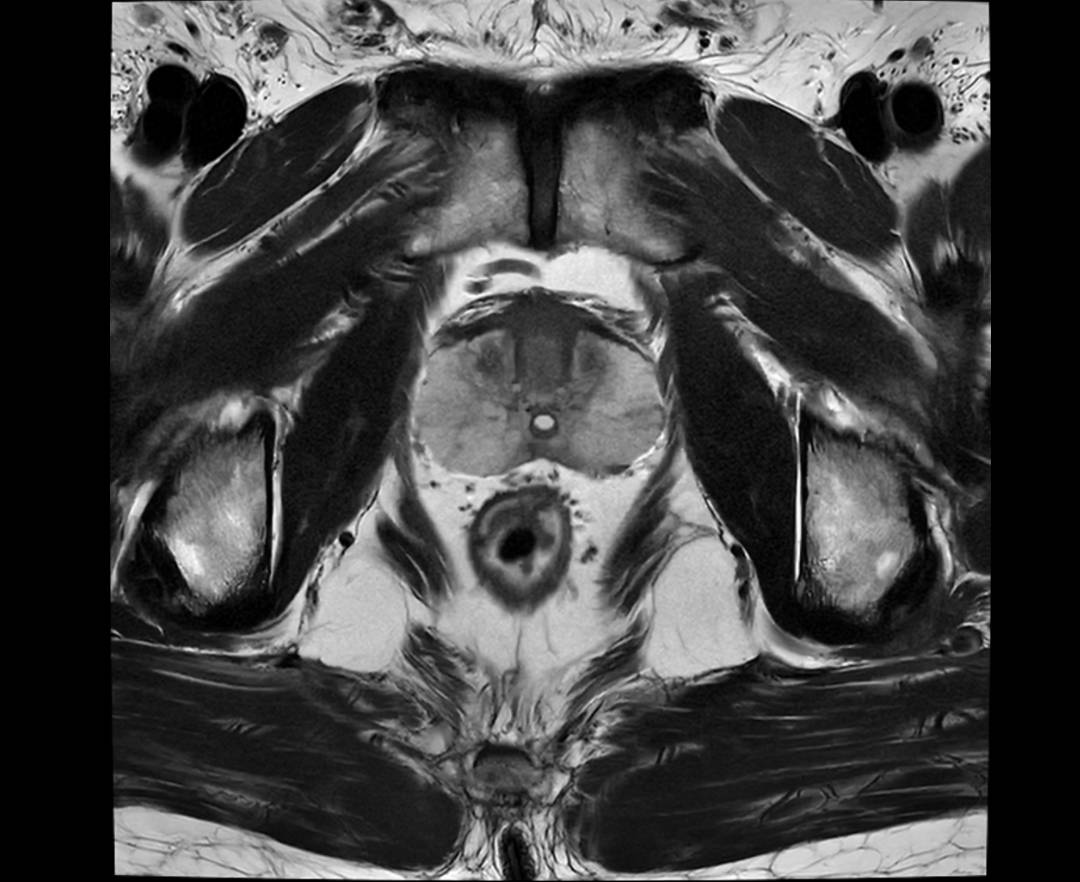

PROSTATE T2 FS TRA

PROSTATE T2 TRA